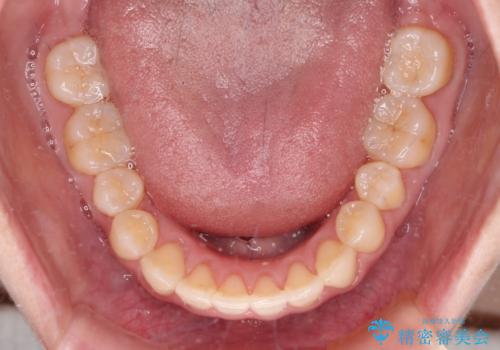

狭い歯列を拡大 拡大装置を併用したインビザライン矯正

インビザラインによる矯正治療を希望されたため、上顎歯列の側方拡大奥歯の遠心移動のための補助装置を併用し、その後はインビザラインにて行うこととしました。

八重歯の動きが鈍く、治療期間は長期化しました。

癒着の疑いもありましたが、アンカースクリューを多用し、何とか改善することができました。